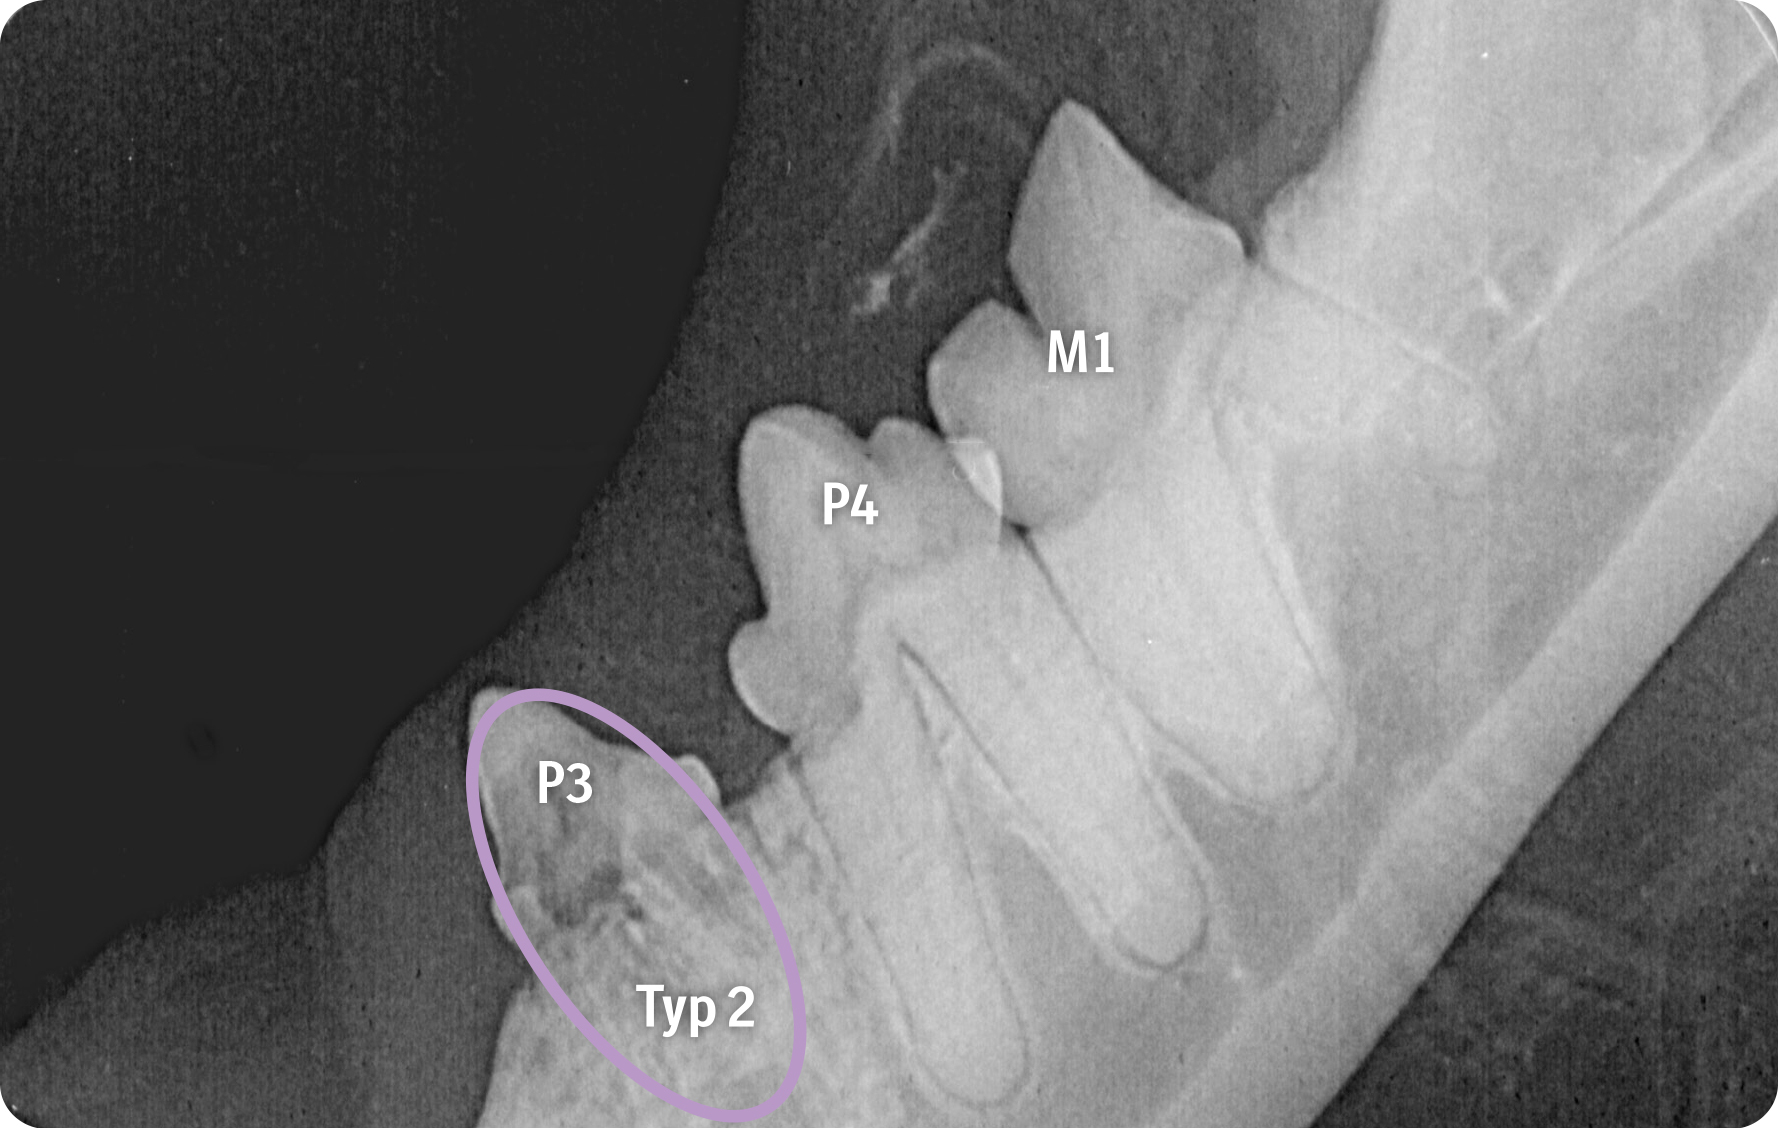

Über entsprechende Röntgenbefunde kann die Zahnresorption aufgezeigt werden. Durch die Visualisierung des Kalenders haben Tierärzt:innen ein gutes Medium, um zu erreichen, dass ihre Botschaft von Tierhalter:innen nicht nur gehört, sondern auch verstanden wird. Wichtig dabei ist die Unterscheidung der einzelnen Typen der Erkrankung. Die intraorale Aufnahme des Unterkiefers rechts zeigt eine Zahnresorption Typ 1 bei M1 mit fokaler Zahnresorption im Kronenbereich sowie den Übergang zur Wurzel bei erhaltenem Parodontalspalt. Bei P3 und P4 werden durch die Aufnahme fehlende Kronenbereiche mit nur noch schwach nachvollziehbaren resorbierten und in Knochengewebe umgebauten Wurzeln erkennbar sowie der Verlust des Parodontolspalts, also eine Zahnresorption vom Typ 2.

Die Bildgebung zeigt, wie unterschiedlich Zahnresorptionen bei der Katze im Röntgen aussehen können. Wichtig für die Praxis zu wissen ist, dass sie je nach Typ unterschiedlich behandelt werden müssen: So ist eine Kronenamputation nur bei einer Typ-2-Zahnresorption mit vollständigem Verlust des Parodontalspalts möglich. Bei Zahnresorption Typ 1, also bei einem erhaltenen Parodontalspalt, müssen alle Wurzeln extrahiert werden.